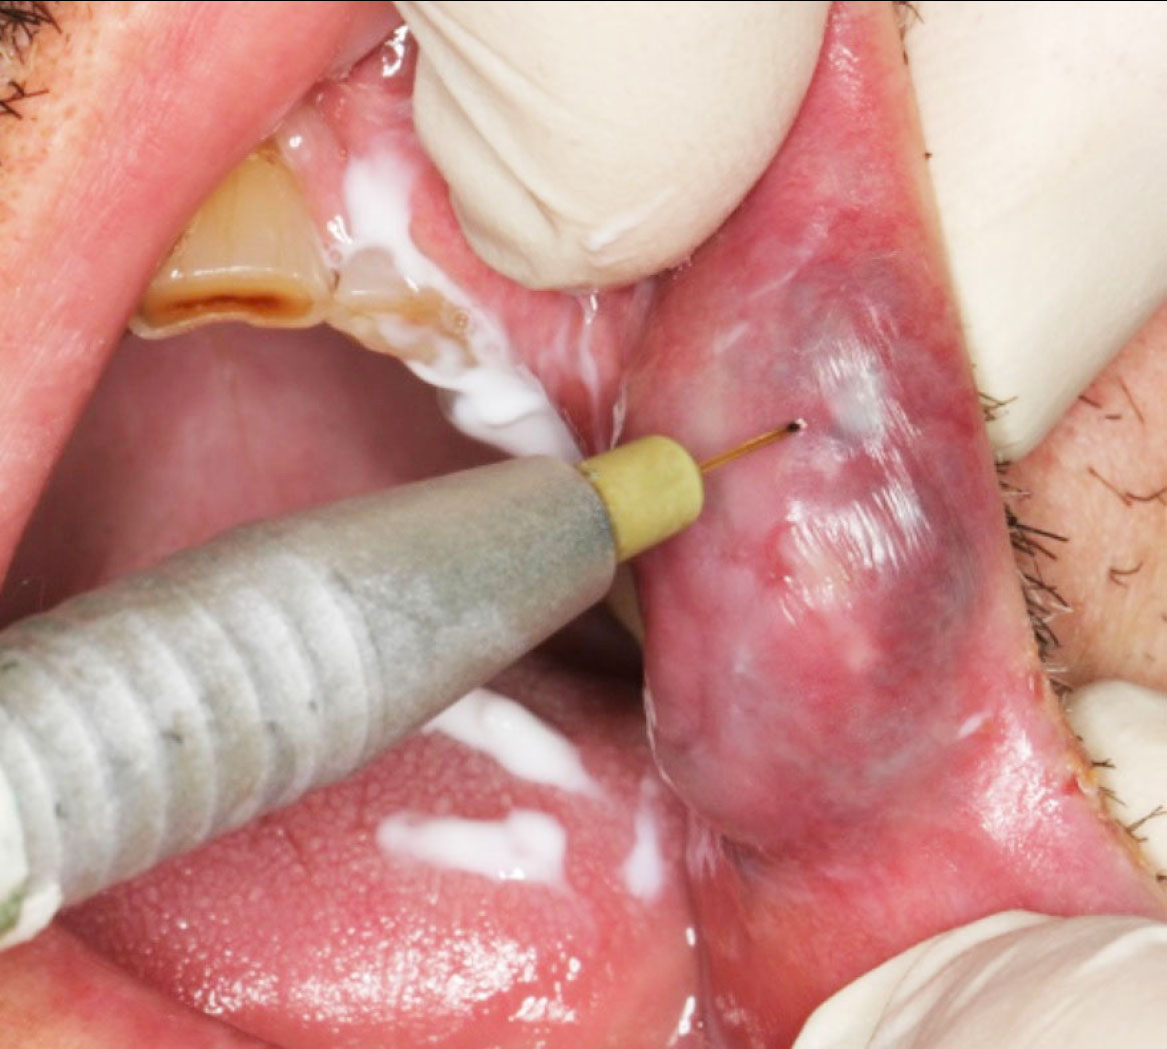

Nello specifico caso illustrato, è stato scelto il trattamento di fotocoagulazione transmucosa mediante laser Nd:YAG (VSP = 100 µsec, fiber 320, power: 2 W, frequency: 20 Hz, fluence: 5 J/cm² , fluence/pulse 0,25 J/cm²). Il fascio laser viene focalizzato e applicato a distanza senza necessità di infiltrazione di anestetico locale, ma solo anestesia di superficie mediante lidocaina in crema (8). Durante il trattamento laser si ottiene un effetto anestetico e ci si può avvicinare e soffermare con il fascio laser per alcuni secondi in più punti a breve distanza (9). L’effetto di fotocoagulazione è visibile. Il risultato è evidente con scomparsa della lesione e totale assenza di sintomatologia post-operatoria al controllo a tre giorni e completa restituito ad integrum con ottimo risultato estetico e funzionale ad una settimana.